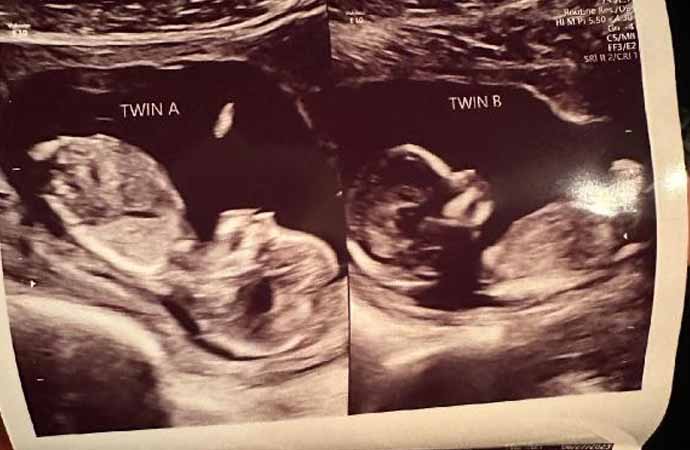

Hatcher'ın doktoru, genç kadının iki rahminde iki ayrı bebeğe aynı anda hamile kalmasının milyonda bir olduğunu söyledi.

Önceki hamileliklerinde sadece tek bir rahminde bebek taşıyan Hatcher, bebeklerin ikiz mi olacağı konusunda henüz bir bilgi veremediklerini söyledi. Durumunu öğrendikten sonra hamileliğini ve sürecini paylaşmak için özel bir sosyal medya hesabı açan Hatcher, bir bağış kampanyası başlattı.